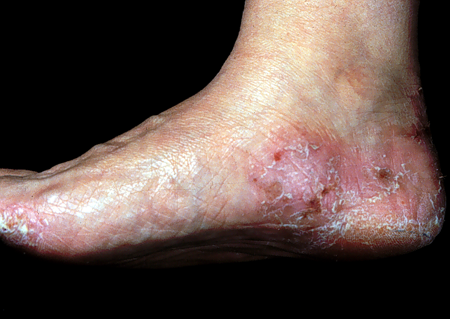

足癣的主要症状为红斑、水疱、脱屑,有的患者还伴有剧烈的瘙痒症状,用手抓破之后会出现糜烂。所以对于一些爱美的女性而言,患了足癣就只能在夏天来临的时候对着漂亮的凉鞋望鞋兴叹。不仅如此,足癣还容易反复发作,较难根治。北京大学第三医院皮肤科副主任医师徐敏丽说,足癣要及时治疗,如果任其蔓延,会严重影响人体健康,甚至会危及生命。

徐敏丽指出,这些做法都是错误的。足癣虽然是小病,但是它不仅影响人们的日常生活,不及时治疗还容易传染到身体的其它部位,引发手癣、甲癣、体癣、股癣等皮肤疾病。此外,足癣还可能引发细菌感染,导致淋巴管炎、淋巴结炎、丹毒等疾病。有糖尿病的足癣患者更是要特别注意,因为糖尿病患者多有血管病变和神经病变,足部皮肤的小破损或癣病都有可能发展成经久不愈的慢性溃疡,甚至发展为坏疽导致截肢。